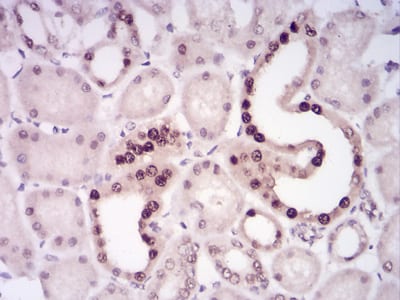

分类: 科研抗体货号: 30876别名: APR; LRP; A2MR; CD91; APOER; LRP1A; TGFBR5; IGFBP3R应用: IHC,IF反应种属: Human